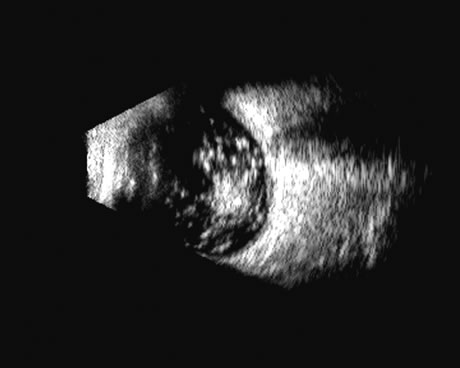

The choroid, like the retina, is highly reflective and may resemble the retina when detached. Its thickness, which includes the retina, Bruch's membrane, and the choriocapillaris (tunica ruyschiana) is not usually differentiable when measured with routine ultrasound;12 however, it may be measured with digital techniques.18 Anatomically, the choroidal elevation is usually a smoothly round, convex surface, limited posteriorly by the vortex veins and anteriorly at any point up to the base of the iris (Fig. 17). The choroidal space should be examined for echoes (blood) or a clear zone, as seen with effusion or the serous part of a hemorrhage. In evaluating membranes from retina or choroid, it is always helpful to repeat the examinations at a later time.

Fig. 17. This patient with a Molteno tube was treated for glaucoma. The top 50 MHz B-scan clearly shows the Molteno Tube (arrow). The bottom 10 MHz B-scan of the same patient demonstrates a choroidal detachment (large arrow) with associated posterior retinal detachment (small arrow). Choroidal elevations are typically convex, highly reflective surfaces with posterior limitation at the vortex vessels. Retina will always attach at the optic nerve. Choroidal elevations are often noted in several quadrants, as seen here.